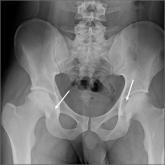

ArticleAnterolateral hip pain • no specific injury • Dx?Author:Patrick Basile, MDPublish date: August 1, 2018► Anterolateral hip pain► No specific injuryRead More